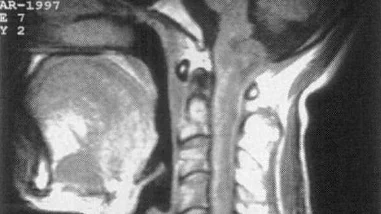

神经鞘瘤是一种源于神经鞘膜细胞的良性肿瘤,常见于成人。其发生率虽不高,但因多在头面部和脊柱等重要部位出现,常导致神经功能的损伤。在临床表现上,患者可能出现面瘫、感觉异常、听力下降等症状。一般情况下,神经鞘瘤的发展较慢,但也有迅速生长、侵袭周围组织的可能。